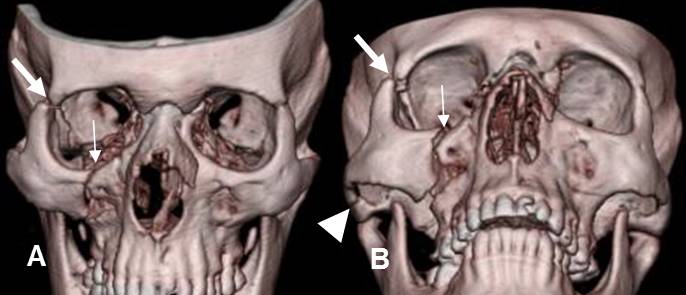

Fig 213. Fractura trimalar.

A y B: TAC reconstrucción 3D. Fractura trimalar con lesión de la unión cigomático-maxilar (Flecha delgada), cigomático-frontal (Flecha gruesa) y cigomática-temporal (Punta de flecha).